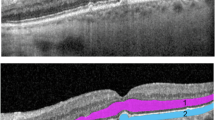

To evaluate functional clinical endpoints and their structural correlations in AMD, with a focus on subretinal drusenoid deposits (SDD).

This prospective study enroled 50 participants (11 controls, 17 intermediate AMD (iAMD) with no SDD, 11 iAMD with SDD and 11 non-foveal atrophic AMD). Participants underwent best-corrected visual acuity (BCVA), low luminance visual acuity (LLVA), low luminance questionnaire (LLQ), scotopic thresholds, rod-intercept time (RIT), photopic flicker electroretinograms and multimodal imaging. Functional and structural relationships were assessed.

Compared with healthy participants, BCVA, LLVA, scotopic thresholds were depressed, and RIT prolonged in iAMD patients with SDD (p = 0.028, p = 0.045, p = 0.014 and p < 0.0001 respectively). Patients with SDD also had reduced scotopic function and delayed RIT compared to iAMD without SDD (p = 0.005 and p < 0.0001). Eyes with SDD and non-foveal atrophy did not differ functionally. Nor did healthy subjects compared with iAMD without SDD. Functional parameters were significantly associated with scotopic thresholds (r = 0.39–0.64). BCVA, LLVA and scotopic thresholds correlated well with ONL volume, ONL thickness and choroidal thickness (r = 0.34–0.61).

Eyes with SDD are surrogate markers of photoreceptor abnormalities comparable with non-central atrophy and should be sub-analysed in clinical trials evaluating potential prophylactic agents to decrease the progression of AMD and may even require different therapeutic interventions.